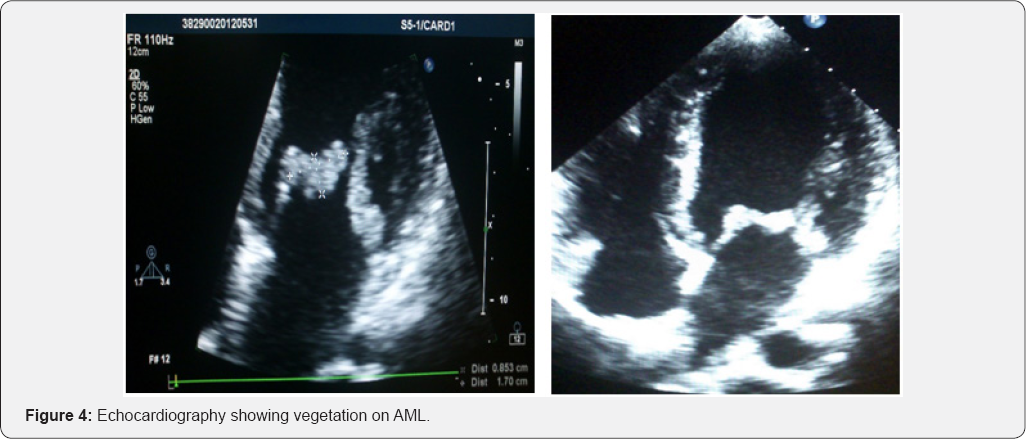

The diagnosis of infective endocarditis was confirmed by evidence of endocardial involvement with echocardiographic demonstration of vegetation attached to the mitral valve (Figure 4), with Janeway’s lesion, Osler’s node & glomerulonephritis. Blood culture failed to grow any pathogenic organism (likely due to initiation of antibiotics at another center on outpatient basis). The patient was treated with intravenous antibiotics (ceftriaxone and gentamicin) with good clinical respon